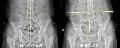

- [»ì¸®´ÂÀÚ¼¼, Á×ÀÌ´ÂÀÚ¼¼] (2) ´ç½ÅÀÇ Ã´Ãß´Â ¹Ù·Î ¼ ÀÖ³ª¿ä? ôÃßÃø¸¸Áõ È®Àιý

- # ÁßÇлý Àڳฦ µÎ°í ÀÖ´Â À̸ð¾¾(45¼¼)´Â °Ç°°ËÁøÀ» ½Ç½ÃÇÑ Çб³·ÎºÎÅÍ ¾ÆÀ̰¡ ôÃßÃø¸¸ÁõÀÌ Àǽɵȴٴ ¿¬¶ôÀ» ¹Þ¾Ò´Ù. Æò»ó½Ã ÇнÀÀÇ ÁýÁßµµ°¡ ¶³¾îÁö°í Ã¥»ó¿¡ ¿À·¡ ¾É¾ÆÀÖÁö ¸ø..